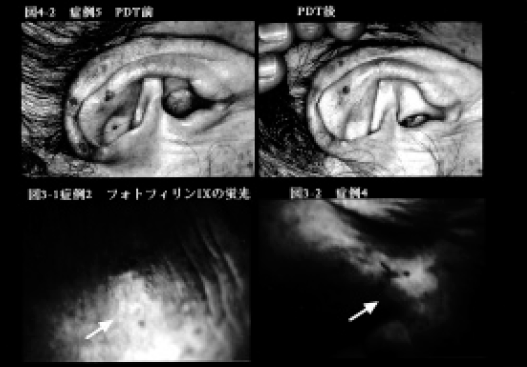

2)菌状息肉症 1例の菌状息肉症(62歳、女性)の体幹に多発する紅斑性浸潤局面(図4-1)に対してPDTを試みた。

20%5 - aminolevulinic acid(5-ALA)含有軟膏を密封塗布(6h)。ハロゲンランプ(500W)にて20分間(120J/cm2)照射した。

日光角化症では1~5回の照射で1週後に皮疹は1~6週で消失(図3-2)、菌状息肉症では2回の照射により4週後には色素沈着を残すのみとなった(図4-3)。6カ月後の現在いずれも再燃をみていない。日光角化症の一例でPDT後のアポトーシス発現を検討した結果(Apotosis Detection Kit、宝酒造使用)、PDT 施行部にアポトーシス陽性細胞が観察されたが、染色態度は均一でなく、なお慎重な検討が必要と思われた。